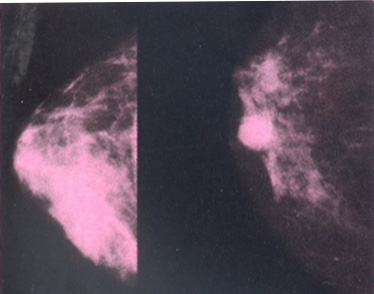

Chỉ phát hiện được nhờ chụp nhũ ảnh: Nhờ một máy dùng tia X để chụp, phát hiện tổn thương ung thư không sờ thấy được.

- Nhũ ảnh: được các bác sĩ chuyên khoa cho chỉ định. Giúp phát hiện tổn thương ở giai đoạn sớm.